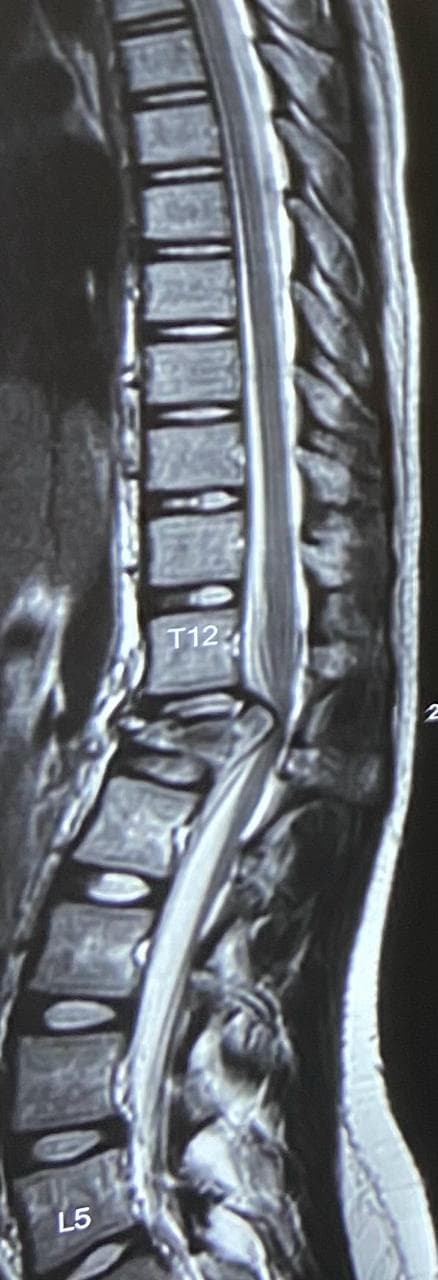

A 17-year-old girl was brought to us after a fall from the first floor of her house. She had sustained a severe injury to her spine and was unable to walk at the time of admission. X-rays and MRI revealed an L1 burst fracture with compression over the spinal cord. On clinical examination, she had paraparesis—weakness of both lower limbs—with significant difficulty in standing and moving. The family was deeply worried as her ability to walk again was uncertain. Given the severity of the spinal cord compression and the risk of permanent neurological loss, she was taken up for emergency posterior stabilization and decompression of the spinal cord